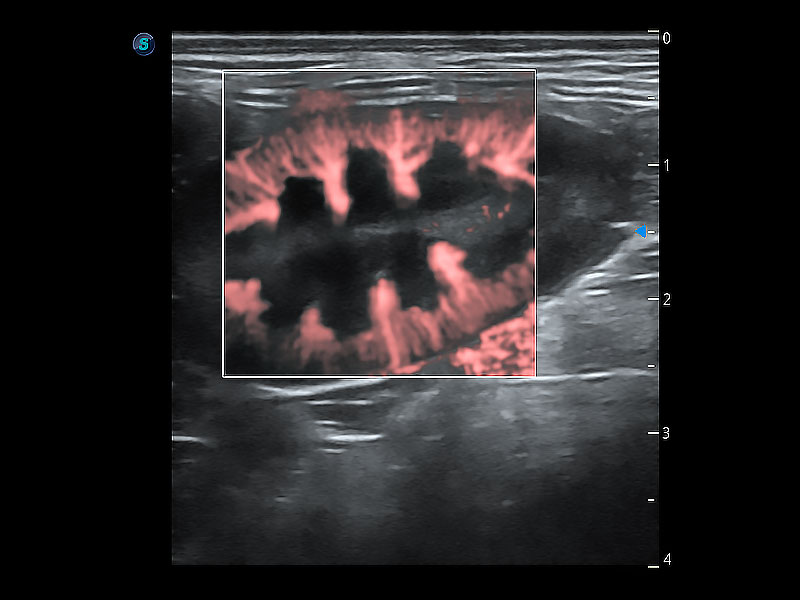

极大提升超低速微细血流的检出能力,同时更精准地滤除软组织和超声信号,为兽用医生提供以往无法通过常规血流获得的疾病诊断信息。

在传统二维血流成像的基础上,呈现血流的立体感,具有动感的生命力之美。即便是微小的血管也能轻松应对,提高了血流的视觉敏感性。

为精细结构及组织边缘提供高清晰度的图像和更大的成像视野。帮助减轻医生的用眼疲劳,快速精准获得测量的数据。